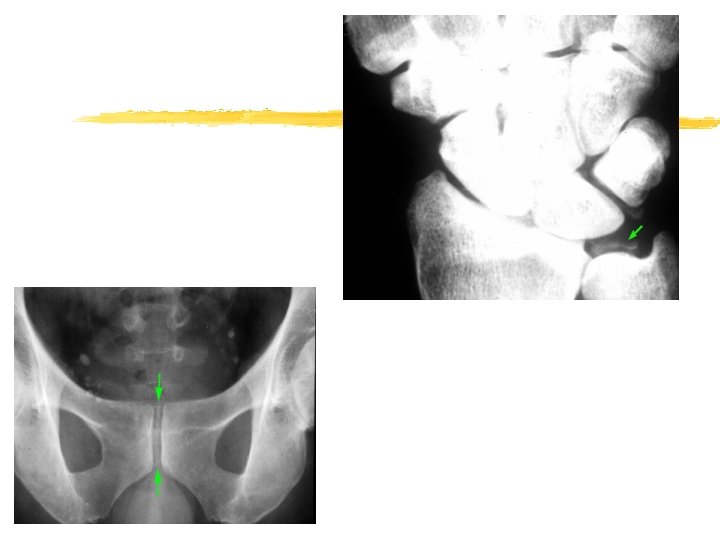

Imaging z Chondrocalcinosis

Pseudo-osteoarthritis z Pattern of joint involvement z Knee, MCP, wrist, elbow , shoulder z More likely to be symmetrical z Chondrocalcinosis

Diagnosis z. Intra- and/or periarticular calcifications zcrystals are very small, and can only be seen by electron microscopy.